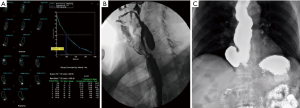

A standardized and validated symptom assessment such as the Eckardt score is useful in evaluation of patients. High resolution esophageal manometry testing should be used for the fine assessment of the esophageal motility, subtypes of the achalasia or characterization of other types of spastic esophageal disorders (Figure 1). The clinical significance of this sub-classification is a subject of debate. A contrast esophagram showing the classic “birds beak” appearance of the narrowed esophagogastric junction and esophageal aperistalsis should be evident (Figure 2A). Patients with spastic achalasia might have a “cork screw” appearance on the esophagogram (Figure 2B). In patients with late or end-stage achalasia, the esophagus may appear significantly dilated, angulated and tortuous alluding to a sigmoidal shape (megaesophagus) (Figure 2C). Megaesophagus has traditionally being approached surgically although it is not an absolute contraindication for POEM, however alternative therapies may be considered due to the increased technical difficulty (11-14). Identification of large amounts of residual food at the initial endoscopy would lead to aborting of POEM procedure to avoid mediastinal contamination (Figure 3).